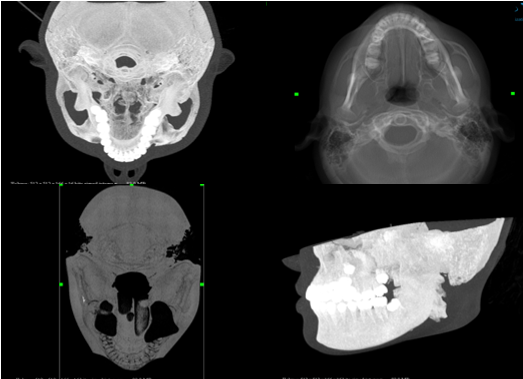

Average Intensity Projection

Average Intensity Projection (AIP)

Her görüntünün ortalama dansite değeri alınarak verinin 2 boyutlu görüntüye aktarılmasıile oluşturulur. AIP ile frontal ya da lateral akciğer grafisine benzer görüntüler elde edilir. Buyöntemle akciğer